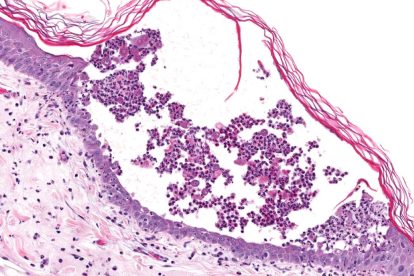

Περίληψη Στη σκωληκοειδή απόφυση, σπανίως, εντοπίζονται νεοπλάσματα, τόσο καλοήθη όσο και κακοήθη, με συχνότερο το καρκινοειδές. Η κλινική τους εικόνα είναι μη...